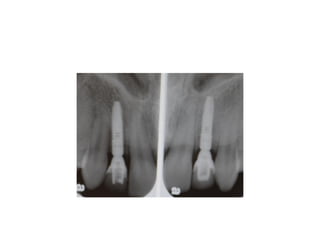

implants are placed w/in restorative

confines